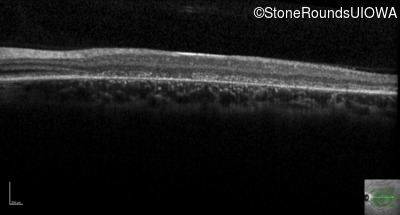

AR Stargardt Disease (IIA)

AR Stargardt Disease (IIA)

| Age at visit: 12 years |

| Age at visit: 13 years |

| Age at visit: 15 years |